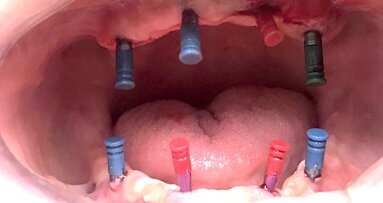

El autor presenta un caso clínico en el que se realizaron ocho exodoncias, restauradas mediante la colocación de cuatro implantes en el maxilar superior y...